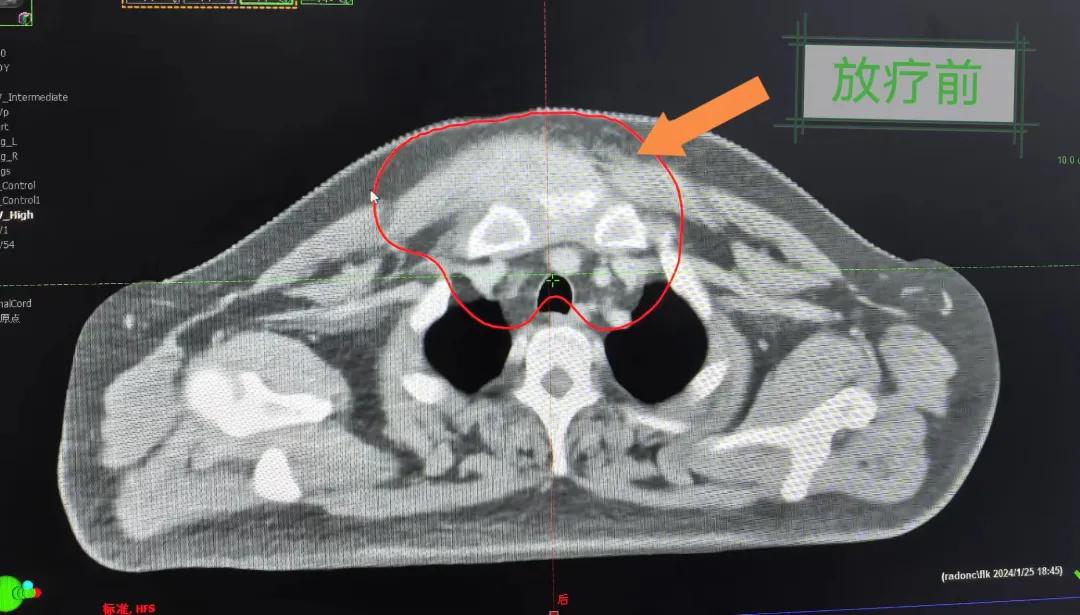

2個(gè)月前,市二院放療科接診了一名特殊的病人。一位40歲的中年男人,其前胸部竟然長(zhǎng)了一個(gè)巨大的大腫塊,已有8cm左右且疼痛。

經(jīng)過(guò)詳細(xì)詢問(wèn)病史,得知患者半年前前胸部突然出現(xiàn)一個(gè)腫塊,最初并未引起重視,以為只是普通囊腫,就隨便抹點(diǎn)藥,貼了膏藥。然而,腫塊并未縮小,反而逐漸增大,并伴隨著難以忍受的疼痛,嚴(yán)重影響了患者的日常生活和工作。隨后就診于當(dāng)?shù)蒯t(yī)院,行“胸部腫物穿刺活檢術(shù)”,術(shù)后病理提示為鱗狀細(xì)胞癌。突如其來(lái)的打擊讓患者不知所措,盡管?chē)L試了保守治療,但效果并不理想,僅能暫時(shí)緩解疼痛。

患者經(jīng)多方咨詢與打聽(tīng),在家屬的陪同下來(lái)到市二院放療科找到趙亮主任尋求幫助。入院后迅速完善了相關(guān)檢查,診斷為罕見(jiàn)的“胸壁腫瘤”。因腫瘤體積大,侵犯周?chē)M織,手術(shù)治療難度較大,經(jīng)院內(nèi)多學(xué)科會(huì)診后,決定采用無(wú)創(chuàng)的局部放射治療。在初步告知患者及家屬治療方案時(shí),病人及家屬都擔(dān)心預(yù)后及放療可能引起的不適,趙亮主任詳細(xì)且耐心的向家屬和病人講述放療過(guò)程中可能出現(xiàn)的不良反應(yīng),確保讓他們安心治療。

隨后,趙亮主任帶領(lǐng)放療團(tuán)隊(duì)以最快的速度完成了患者的放射治療計(jì)劃,在保證放療精準(zhǔn)打擊腫瘤的同時(shí),利用先進(jìn)的三維立體精確放療技術(shù),最大限度的避免心臟、肺部的損傷發(fā)生,整體治療精準(zhǔn)度達(dá)到1mm以內(nèi)。經(jīng)過(guò)10次的放射治療后,患者疼痛已明顯減輕,胸部腫物肉眼可見(jiàn)的縮小,患者及家屬臉上終于露出久違的笑臉。

治療期間,患者沒(méi)有出現(xiàn)明顯不適,治療結(jié)束后,患者胸壁腫物由最初8cm縮小至約1cm,后患者至外科行手術(shù)治療。